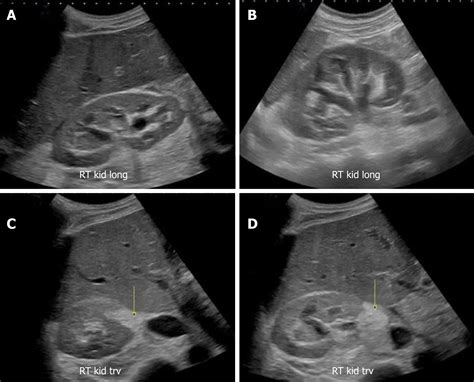

To determine if a kidney is within the healthy range, radiologists and nephrologists rely on ultrasound, CT scans, or MRI technology. These diagnostic tools allow clinicians to measure the length, width, and thickness of the organ accurately. In a healthy adult, a normal sized kidney typically measures between 10 to 12 centimeters in length. Anything significantly smaller may indicate chronic kidney disease or atrophy, while an unusually large kidney could point toward conditions like hydronephrosis, polycystic kidney disease, or renal tumors.